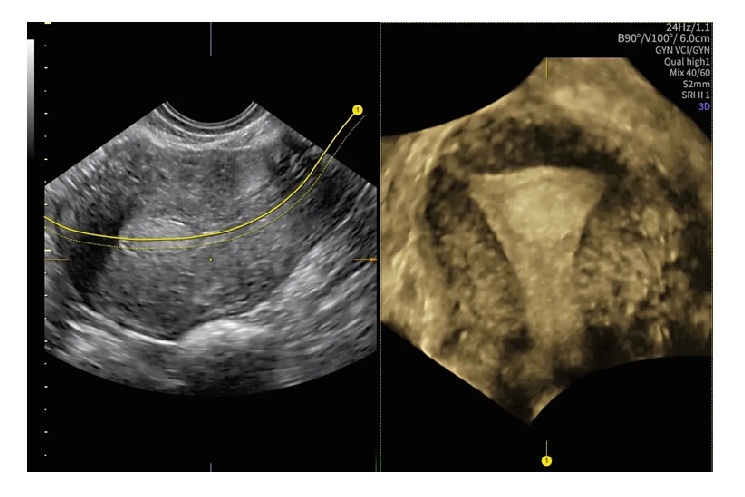

産婦人科向け超音波画像診断装置「Voluson Performance 18」

「Voluson Performance 18」は、検査時間の短縮するAI(人工知能)を活用して開発したソフトウエアと自動化ツールを搭載。子宮筋腫と子宮、子宮内膜の位置関係を立体的に表示する「Fibroid Mapping(フィブロイド・マッピング)」や、線を引くだけで子宮の断面を自動的に表示する「Uterine Trace(ユーテリン・トレース)」など、正確な診断を支援する機能を備える。